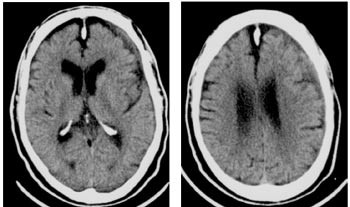

Pasienten kunne imidlertid fortelle at samboeren var sjalu og hadde gjemt danseskoene hans. Neste uke fortalte han triumferende at nå hadde han funnet danseskoene igjen og hadde gjemt dem i garderobeskapet på dagavdelingen, så nå ville han gjerne delta i dansen. Ved poliklinisk undersøkelse etter et halvt år viste CT-undersøkelsen av hjernen nærmest normale forhold (fig 3).